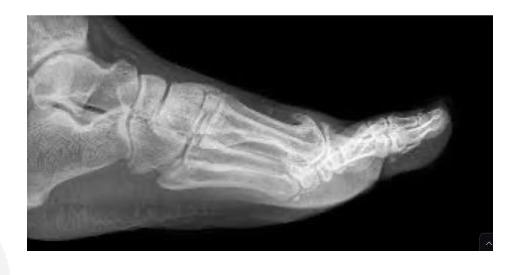

Calcaneal Fractures

Calcaneal Fracture

Complications: If displaced, can lead to osteoarthritis of subtalar joint which is painful Evaluation: CT scan to assess displacement Treatment: Conservative management

Calcaneal Fracture Evaluation

Q2: What other image you need for better evaluation of fracture?

- Calcaneal fracture

- CT scan to show the displacement